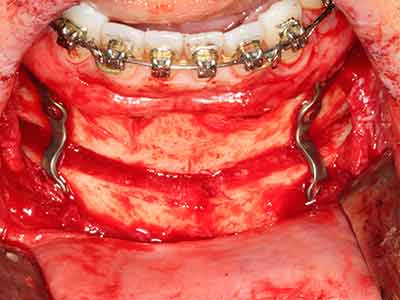

Bei der Knochenblockentnahme zeigen sich weitere Vorteile für die Piezochirurgie: Neben der bereits beschriebenen hohen Präzision bei der Osteotomie stellt sich gerade die Verwendung der dünnen Sägespitzen als besonders materialschonend heraus. Bei der Verwendung insbesondere von Lindemannfräsen sind mit deutlich höheren Entnahmeverlusten durch die dickere Instrumentenspitze zu rechnen (Lakshmiganthan, Gokulanathan et al. 2012). Die insbesondere bei retromolar entnommenen Blocktransplantaten notwendige basale Abtrennung wird durch speziell hierfür vorgesehene rechtwinklige Sägen erleichtert, so dass die Piezochirurgie als präzises, übersichtliches und sicheres Verfahren zur retromolaren Knochenblockgewinnung angesehen wird (Happe 2007) (Abb. 1-12).

Knochengewebe ist nicht nur rein mineralisch, sondern auch in wesentlichen Anteilen aus Kollagenfasern aufgebaut. Dies gewährleistet neben einer guten Druckfestigkeit eine gewisse Flexibilität, welche für die Durchführung von Augmentationen genutzt werden kann. Bei der klassischen Expansionsplastik im Sinne eines Bone Splittings wird der atrophierte Kieferkamm in seiner Längsachse gespalten und nach Erreichen einer ausreichenden Osteotomietiefe vorsichtig aufgedehnt (Abb. 13-16), idealerweise ohne den Kiefer wesentlich zu deperiostieren (Brugnami, Caiazzo et al. 2014, Stricker, Fleiner et al. 2014). Bewährt haben sich Schrauben- und Plattensysteme mit zunehmender Expansionsdistanz, um die beiden Knochenlamellen unterhalb der Bruchschwelle voneinander zu distanzieren. In der Regel werden Restknochenbreiten von mindestens 3-4 mm gefordert (Chiapasco, Zaniboni et al. 2006), um eine ausreichende Flexibilität und knöcherne Bedeckung der einzubringenden Implantate zu gewährleisten. Ggf. kann eine ein- oder beidseitige vertikale Entlastungsosteotomie die Flexibilität verbessern. Als Alternative zur klassischen Technik wurde eine Kombination mit weiteren augmentativen Techniken vor allem auf der bukkalen Seite beschrieben.

Mittels Piezosägen erfolgt die Anlage des Splittings besonders schonend und ohne wesentliche Dimensionsverluste, so dass sich keine signifikanten Unterschiede von Implantaten im gesplitteten Kiefer im Vergleich zum nicht defizitären Alveolarkamm gezeigt haben (Chiapasco, Zaniboni et al. 2006, Danza, Guidi et al. 2009). Gerade beim lokal begrenzten und tiefen Splitting ist jedoch stets auf eine ausreichende Wasserkühlung zu achten, um thermische Belastungen in den apikalen Osteotomiebereichen zu vermeiden.